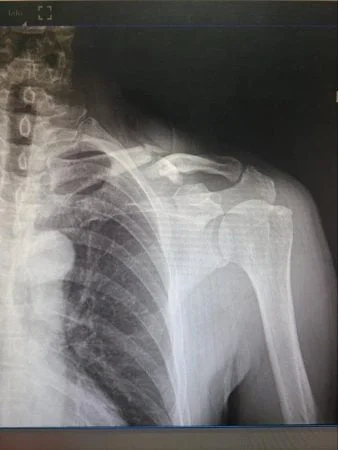

Tuy nhiên, để chẩn đoán chính xác tình trạng gãy xương đòn vai, bác sĩ không chỉ dựa vào những triệu chứng lâm sàng nói trên mà còn cần thực hiện một số phương pháp khác như chụp X-quang thẳng nghiêng xương đòn. Kết quả chụp X-quang sẽ giúp bác sĩ xác định được vị trí gãy, đường gãy và các tổn thương kèm theo.